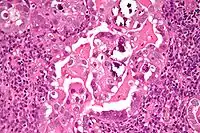

Histopathologically, uterine serous carcinomas is typically characterized by (1) nipple-shaped structures (papillae) with fibrovascular cores (2) marked nuclear atypia (irregularities in the nuclear membrane, enlarged nuclear size), (3) psammoma bodies and (4) cilia.